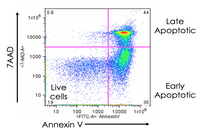

- Evaluation of cell apoptosis by flow cytometry

- Examination of living and dead cells